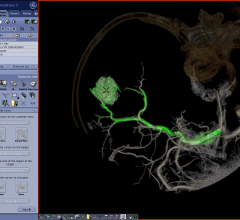

December 2, 2015 — Philips announced IntelliSpace Portal 8.0, the latest edition of its advanced data sharing, analytics ...